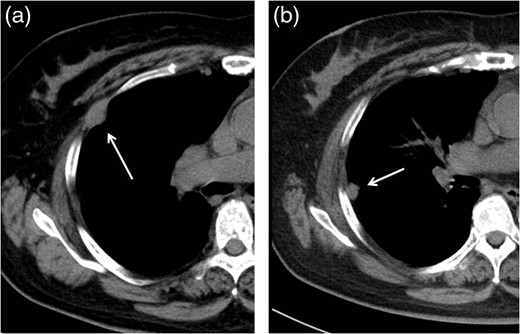

Follow-up CT performed 36 months after the operation revealed two pleural tumors located near the second and third ports (Fig. 2a and b). We suspected the pleural recurrence of thymoma and performed a second operation. Initially, the operation was performed only by VATS with three ports. After removing the severe adhesion between the lung and chest wall, we were able to identify the two tumors. As with the extrapleural tumor, the tumors arose from the intercostal space. Their surfaces were covered with parietal pleura with partial irregularity (Fig. 3). There were no other recurrent findings in the thoracic cavity. Given these findings, we diagnosed these tumors as port-site implantations after the first VATS.

In the operative findings, the tumors were found to have arisen from the intercostal space, and their surfaces were covered with parietal pleura with partial irregularity.